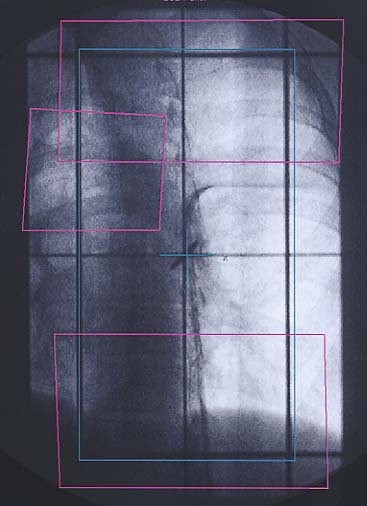

Mammakarzinom: Simulationsbild

Einführung aktuelle Bilder - Einführung Bestrahlungspläne - Einführung Demonstration